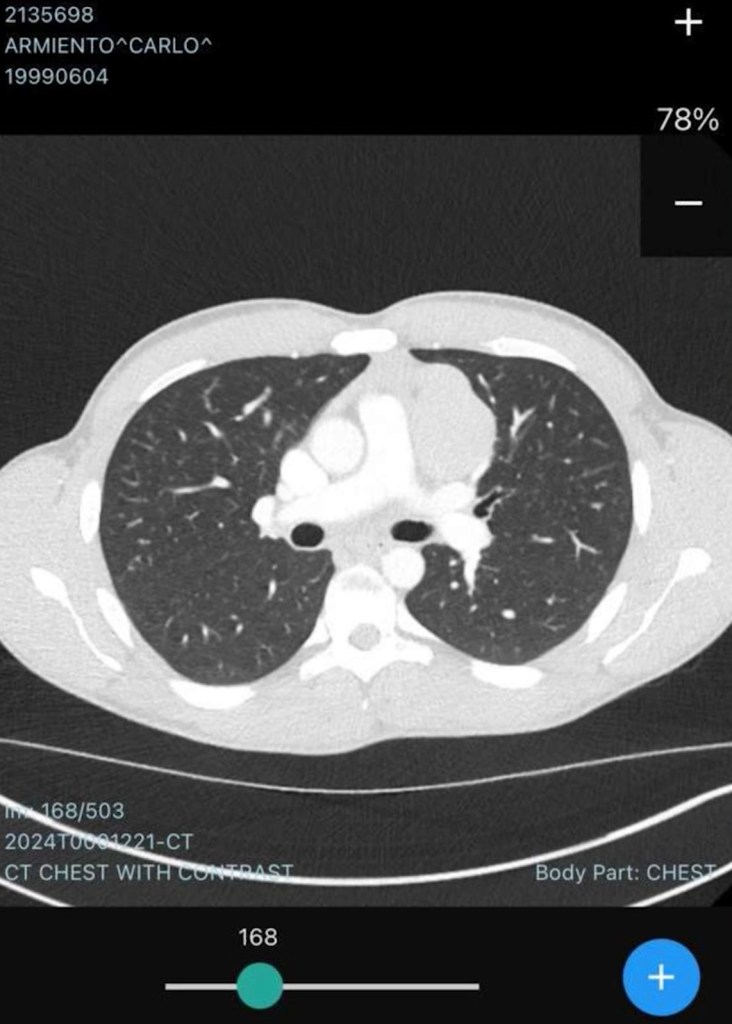

The 26-year-old was in his second season at Brisbane Roar when, in March 2024, a persistent cough led to a chest X-ray and the discovery of a nine-centimetre mass in his lung, and his cancer diagnosis.

So, I went to get an X-ray at Brisbane, when I was there, and they found a nine-centimetre mass inside my lung and at the time I thought it was nothing, it was just maybe a virus or something, not cancer-related.